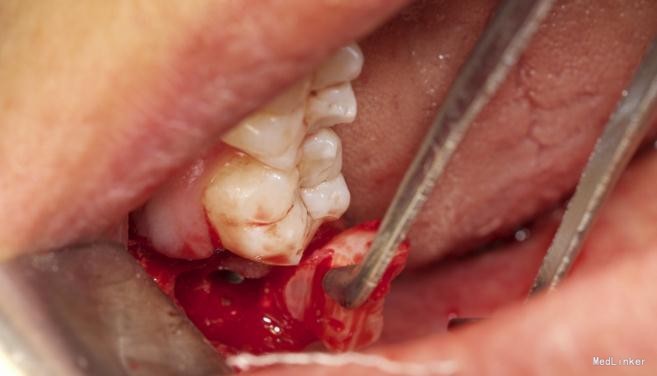

患者,男,25岁,要求拔除左下颌水平阻生牙齿,平素体质一般,无药物、食物过敏史,无高血压、心脏病等系统病史

拔除术

效果很好,患者满意

详尽的病例,值得学习。水平阻生的智齿应该尽早拔除,以免后患,极容易在7和8之间形成食物嵌塞而导致7的远中邻面龋坏。8远中的盲袋也易导致冠周炎

水平阻生拔除的难度还是很大的,图片看着创伤不是很大,能不能把您拔牙时的阻力分析和该牙具体的拔牙步骤给我们说一下呢?谢谢~